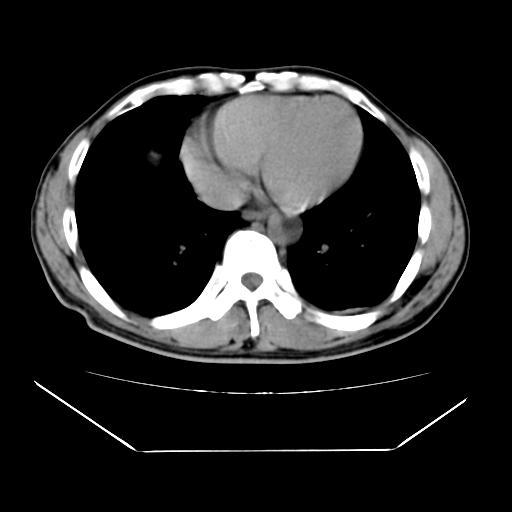

男性,55岁,外院体检afp明显升高,但b超未发现异常,否认乙肝病史。来我院ct增强。有延时扫描。

肝脏右叶动脉期可见低密度影,至延迟期被充填,考虑血管瘤可能性大。

肝右叶病灶

不排除肝右叶肝癌可能。

如果这个是癌灶的话则下腔静脉有瘤栓可能

肝6段血管瘤

血管瘤可能性大。

考虑肝右静脉影。